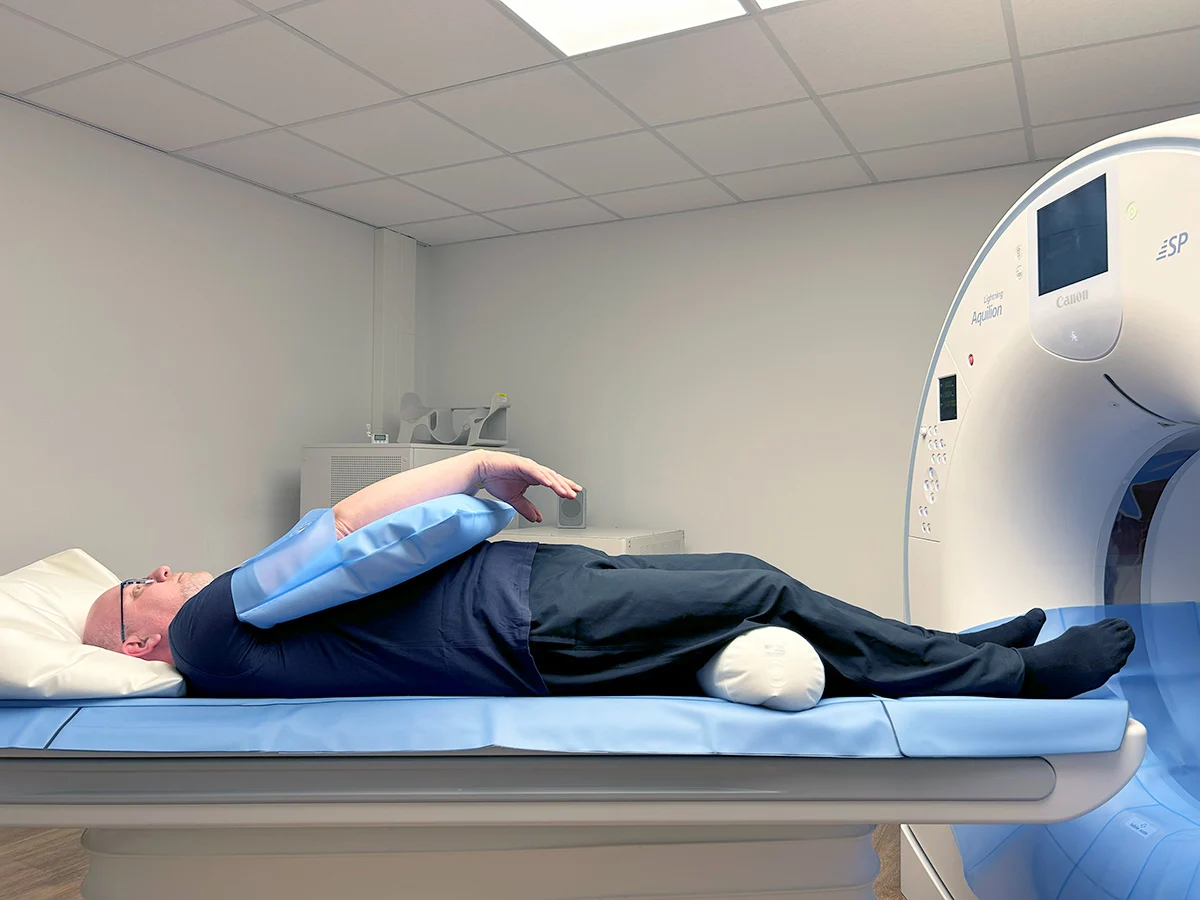

![CT Scan Cost in Dubai: Prices, Types & What to Expect [2026]](/wp-media/blog/ct-scanner-patient.webp)

CT Scan Cost in Dubai: Prices, Types & What to Expect [2026]

CT scan costs in Dubai from AED 800–3,500. Compare prices for brain, chest, abdomen, spine CT scans. Preparation, results, and insurance coverage guide.

CT Angiogram Cost in Dubai: Pricing Guide 2025

CT angiogram pricing in Dubai with detailed cost breakdown, insurance coverage guide, DCDC pricing, and what's included in the scan package.

How to Prepare for a CT Angiogram: Checklist

CT angiogram preparation checklist: caffeine avoidance, medication instructions, fasting requirements, heart rate targets, and what to bring.